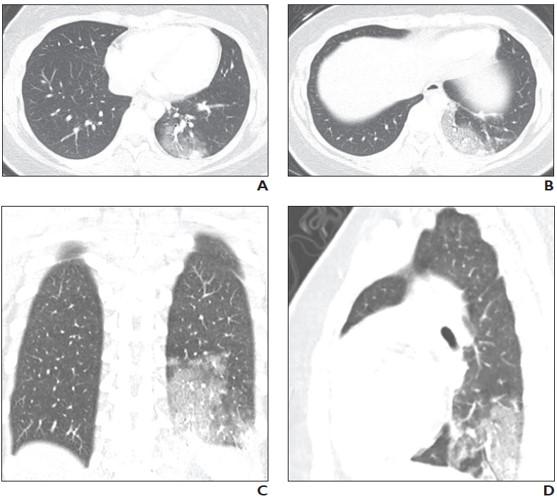

Similarly, while the literature describing chest CT findings in patients with COVID-19 are more robust than those describing chest radiography findings, only a few articles have reported CT findings of COVID-19 in children.

A study of 20 pediatric patients with COVID-19 reported that the most frequently observed abnormalities on CT were subpleural lesions (100% of patients), unilateral (30%) or bilateral (50%) pulmonary lesions, GGO (60%), and consolidation with a rim of GGO surrounding it, also known as the halo sign (50%).

The authors of this AJR article also pointed to a smaller study of five pediatric patients with COVID-19, where investigators reported modest patchy GGO, one with peripheral subpleural involvement, in three patients that resolved on follow-up CT examination.